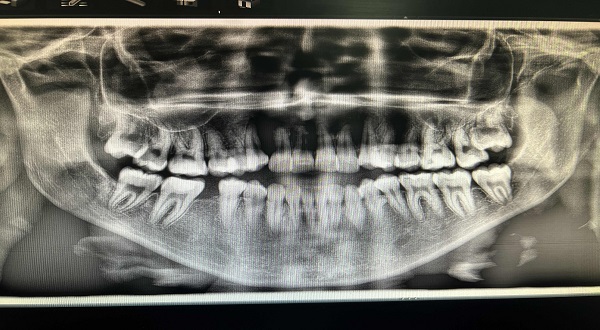

● تواجد العظام بنسبة غير كافية في الفك في المنطقة المراد زراعتها

● التأكد من وجود العظام المراد إتمام عملية الزراعة فيها على مسافة كافية من الجيوب الأنفية وكذلك أعصاب الفك